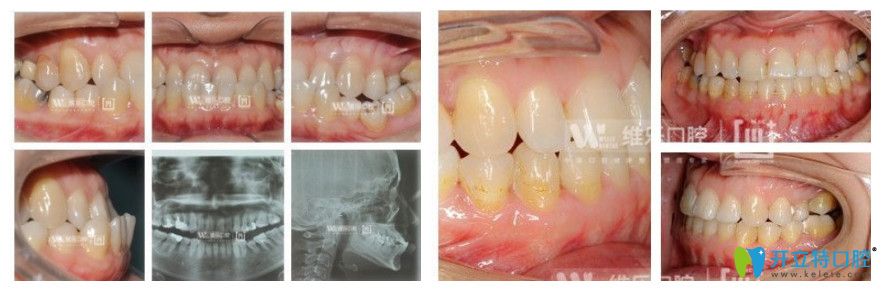

案例三:38歲女性地包天矯正

牙齒問題:上頜后縮,下頜前突,全列牙反頜,咬合不佳。

矯正方式:金屬自鎖托槽矯正

維樂口腔8歲女性地包天矯正前后對(duì)比圖

顧客感言:通過矯正后,牙齒反頜解除,咬合問題解決,面型得到明顯改善。